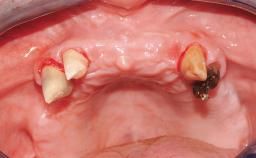

Rehabilitating an Edentulous Maxilla with a Fixed Dental Prosthesis Following Provisional Immediate Loading

This case features the flapless computer-guided placement of 7 bone-level implants, distributed to provide maximal support for the prosthetic framework. A rigid one-piece metallic framework was utilized as an interim restoration to reduce the risk of fracture associated with this prosthetic design. As part of the clinical examination, the SAC Assessment Tool was used, resulting in a surgical and restorative risk classification as “complex”.